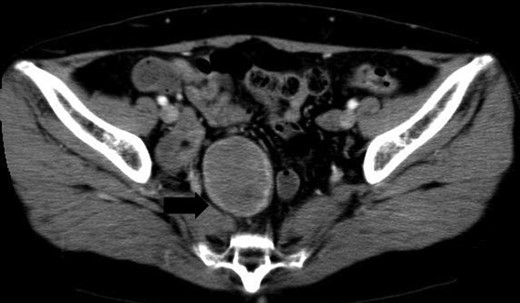

A 54-year-old woman was referred to our hospital with a mass in the pelvic cavity detected on chest-abdominal, CT done for investigation of breast cancer. She had no particular past and family history, and the physical examination was unremarkable. Ultrasonography of the pelvis revealed a 5 × 4.3 cm, solid mass separated from her right adnexa (Fig. 1). Contrast enhanced-CT showed a 5 × 4 cm, solid, well-defined, heterogeneous mass in the right side of the pelvic cavity (Fig. 2). MRI showed that the tumor demonstrated homogeneous hypointensity on T1-weighted images and heterogeneous slight hyperintensity on T2-weighted images (Fig. 3a and b). Sagittal sections of MRI demonstrated that the mass was intricately related to the anterior presacral fascia (Fig. 4). The preoperative diagnosis was a mesenteric gastrointestinal stromal tumor.

Contrast enhanced-CT shows a 5 × 4 cm solid, well-defined, heterogeneous mass in the right side of the pelvic cavity.